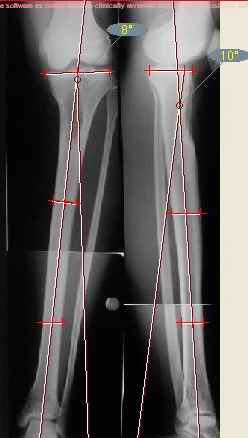

Спасибо за схемы. Не уверен, что удастся разобраться по одним картинкам. Можно попросить прокомметировать иллюстрации?